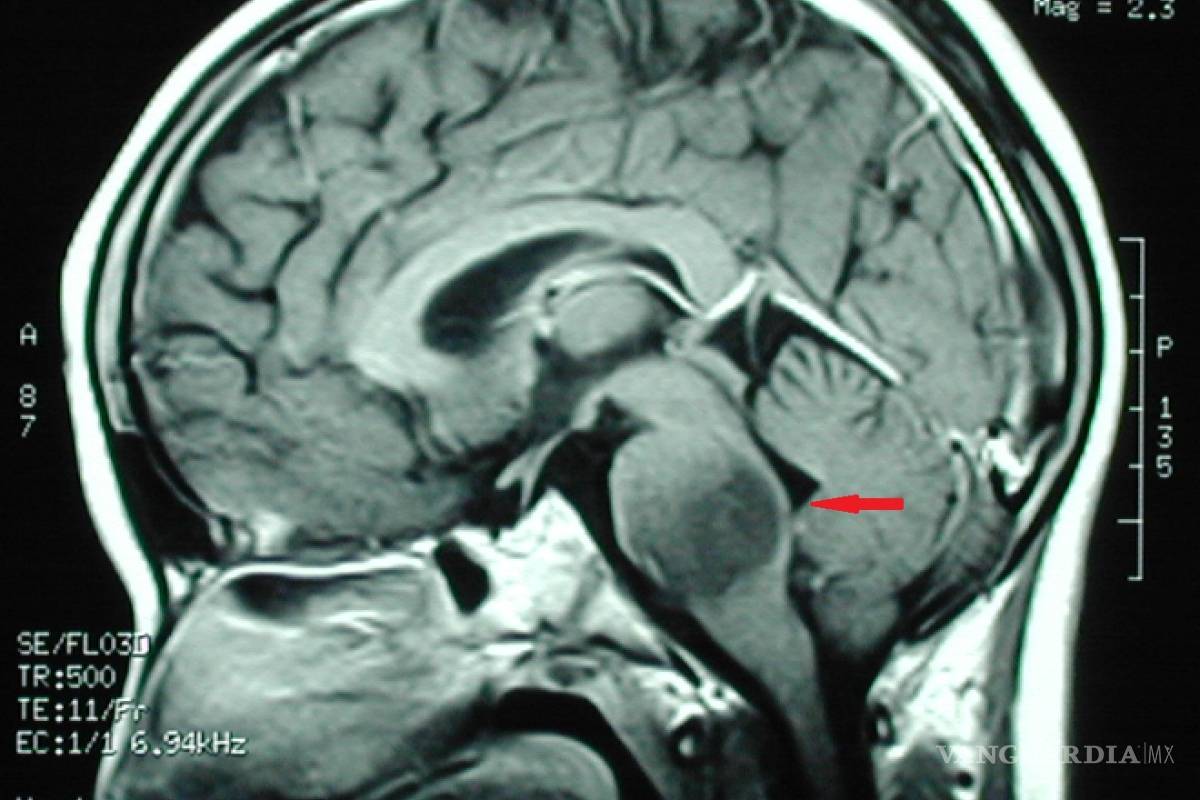

Los especialistas dieron a conocer que el tratamiento se basa en utilizar una mezcla de medicamentos que, en cierta secuencia, causan un efecto positivo en el tratamiento de los gliomas de tallo cerebral

Quienes padecen de esa enfermedad presentan un tumor que se llega a calificar como inoperable, sin embargo, los médicos de Monterrey, con una experiencia de 20 años trabajando de la mano, desarrollaron un procedimiento denominado quimioterapia intraarterial superselectiva, la cual ha dado una esperanza de vida a sus pacientes de todo el mundo.

En entrevista, los especialistas dieron a conocer que el tratamiento se basa en utilizar una mezcla de medicamentos que, en cierta secuencia, causan un efecto positivo en el tratamiento de los gliomas de tallo cerebral o incluso de otros tumores cerebrales.

Luego, explicaron, se hacen estudios de imagen para monitorear el avance que presentan los pacientes y en caso de no encontrarse actividad tumoral, se suspende el tratamiento y continúa en observación el paciente.